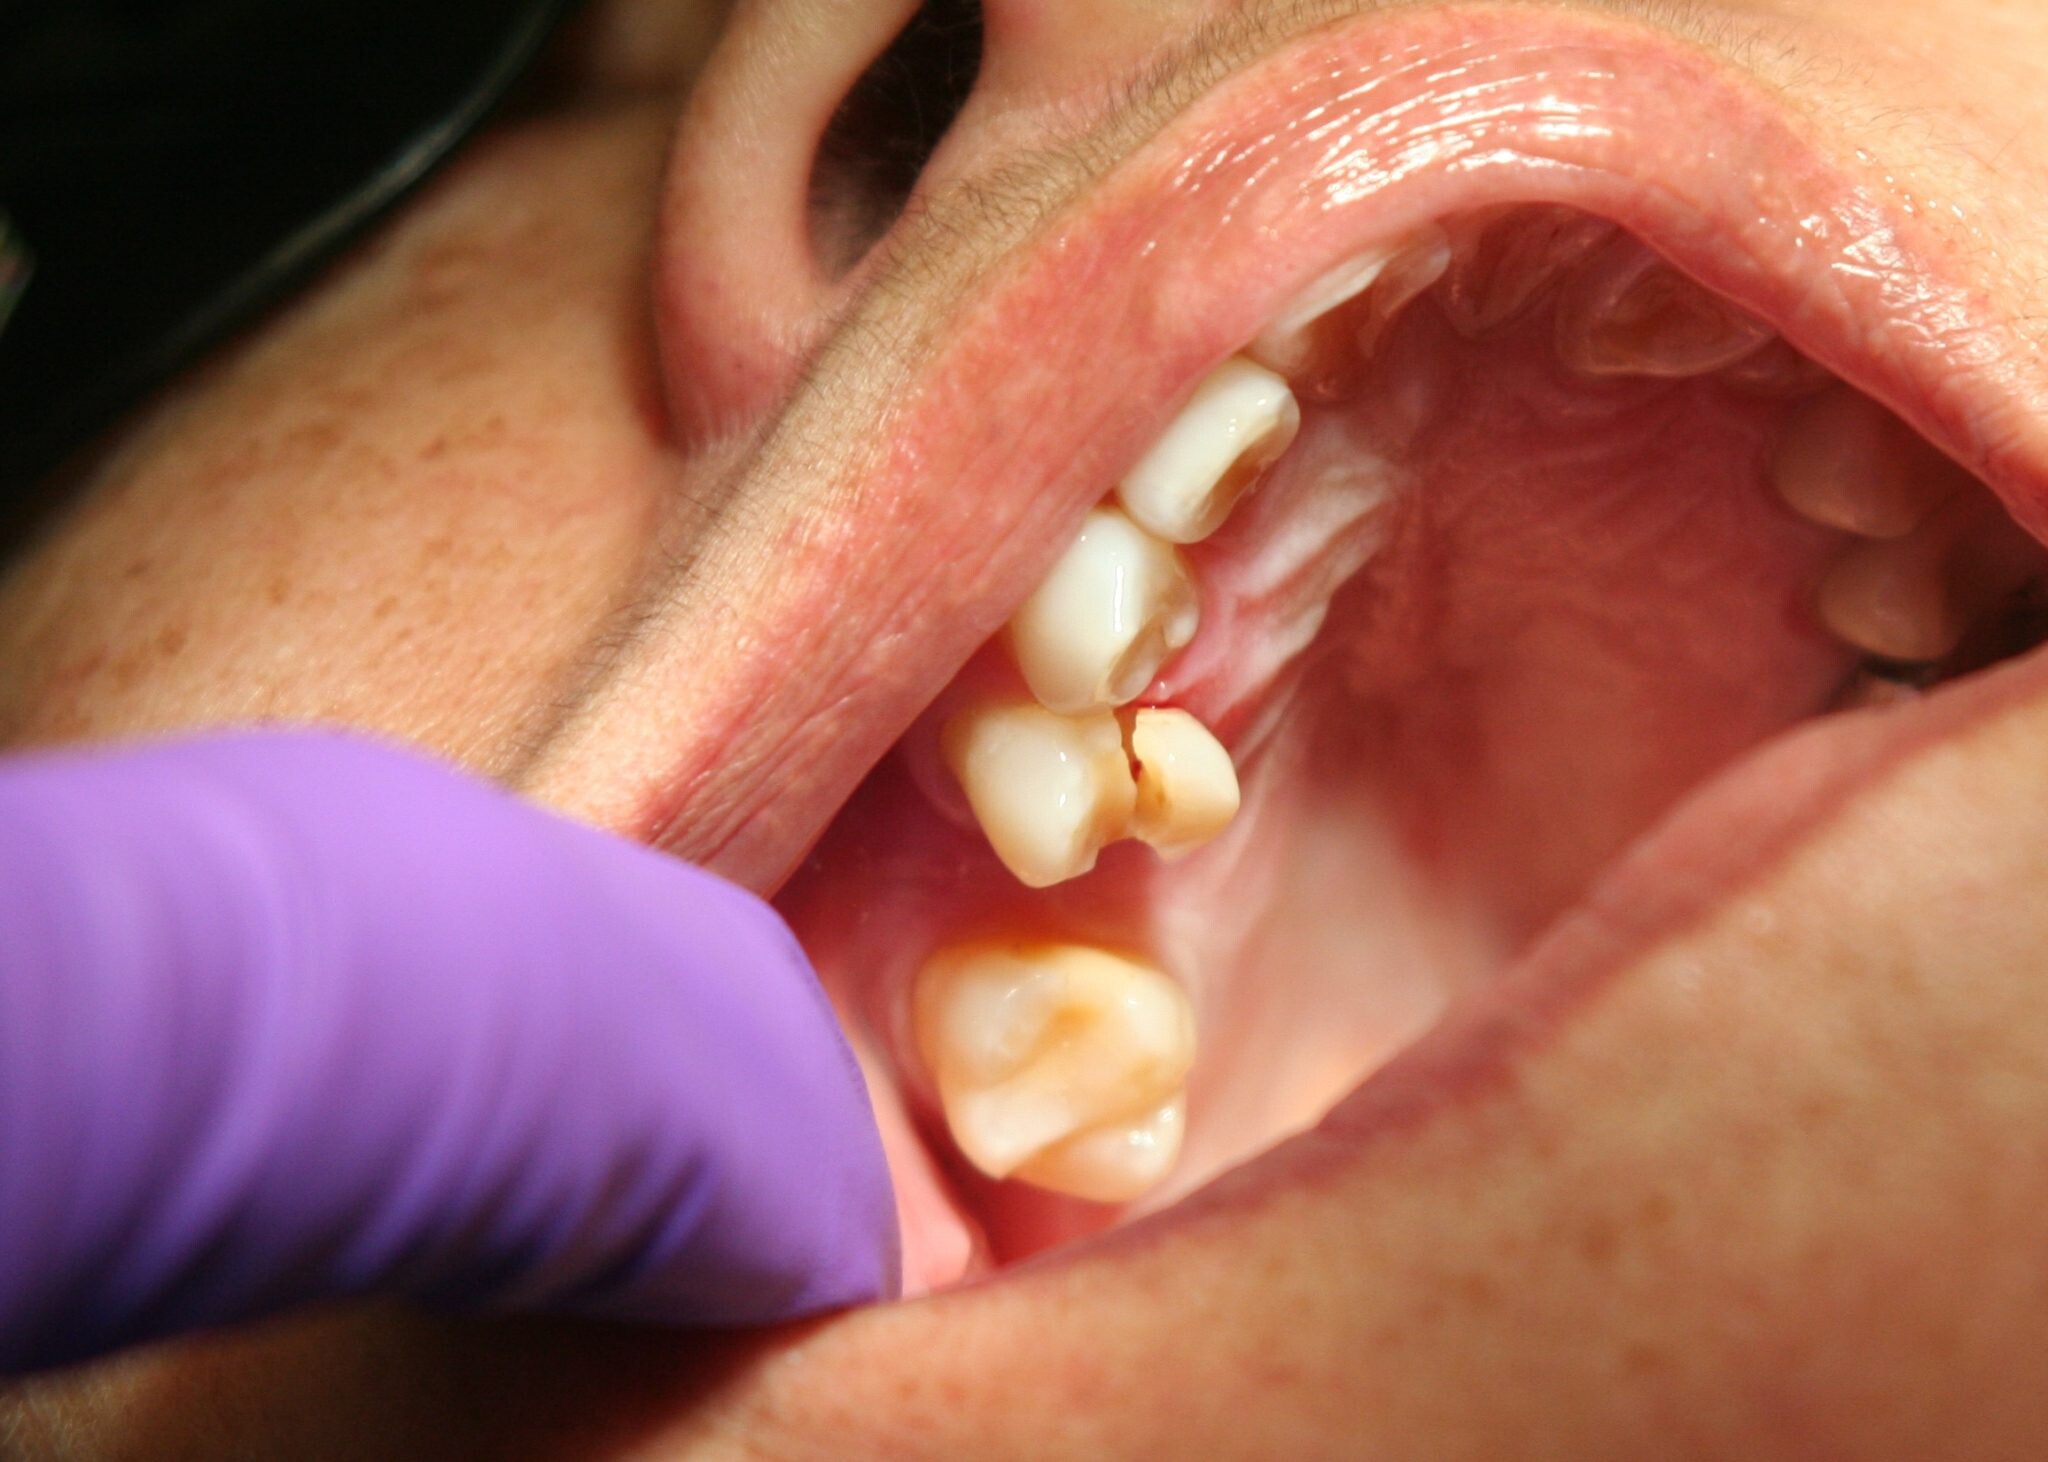

In some cases, jaw pain on one side can indicate underlying oral health problems. Some common issues that cause jaw pain are cavities, an abscessed tooth, gum disease, tooth decay, growth of wisdom teeth, missing or crooked teeth, and clenching or grinding your teeth.

Mutilates the Neighbouring Teeth

Since there is not enough room for the tooth to grow, it will case the teeth to grow in an abnormal manner. This results in impaction of the teeth, giving rise to many other oral problems. When the wisdom tooth emerges against the second set of molar, it might damage them, increasing the risk of acute infection. It will also have an effect on other teeth, which will intensify the need for an orthodontic treatment to align the other teeth.

Tooth Decay

The fully impacted or the partially impacted wisdom teeth are at greater risk of tooth decay, than other teeth. This usually happens, because of the location of the wisdom tooth, especially towards the back of the mouth, which is hard to clean. Moreover, since it lies at the back of the mouth, there are chances of food getting easily trapped between the gums and the tooth, promoting the growth of bacteria.